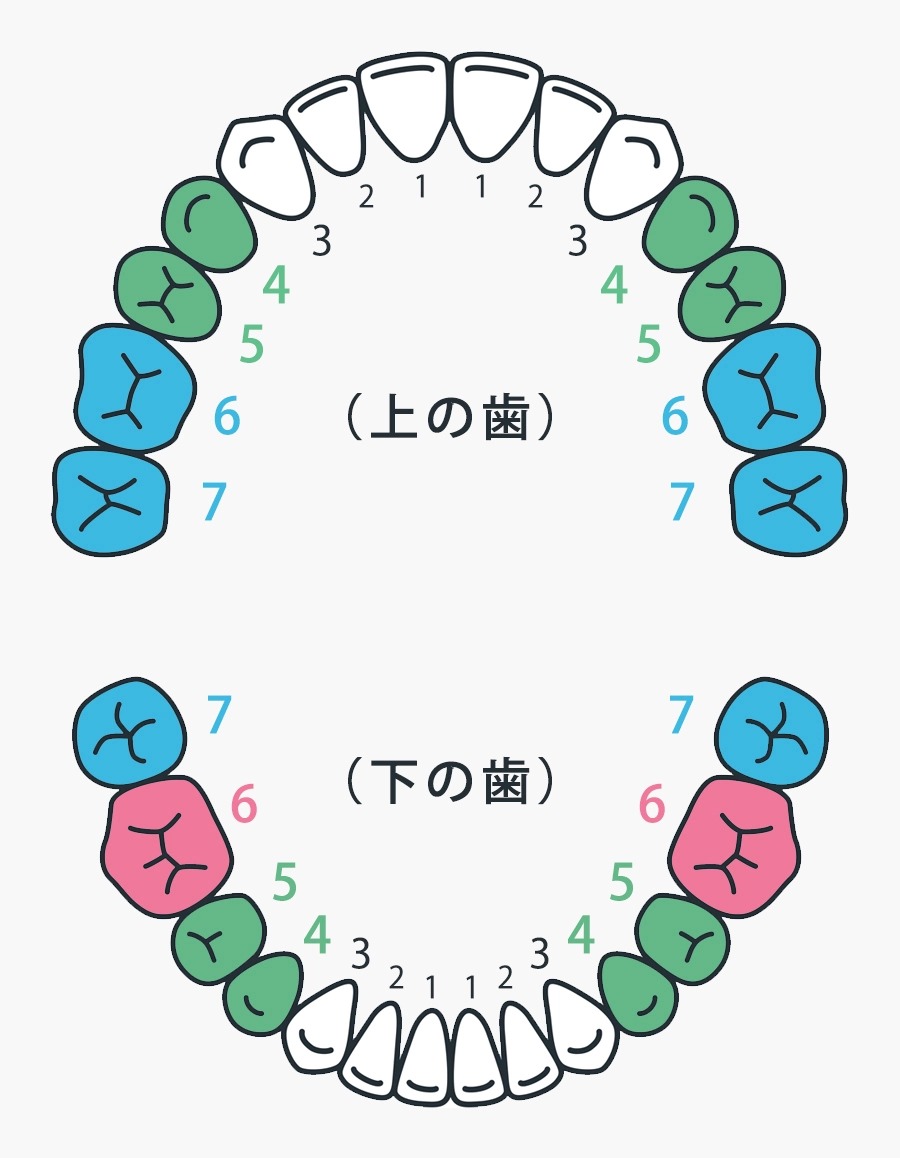

CAD/CAM冠を保険適用で使える歯

健康保険適用の歯

【緑】上下の4番・5番の歯

小臼歯という部位になり、健康保険適用で白いかぶせものが選べます。

【ピンク】下の6番の歯

7番の歯が4本とも残っている場合、健康保険適用で白いかぶせものが選べます。

金属アレルギーの方

【青】上の6番の歯、上下の7番の歯

【ピンク】下の6番の歯

金属アレルギーの方は、健康保険適用で白いかぶせものが選べます。

※金属アレルギーを証明する医師の診断書が必要となります。